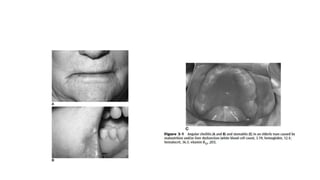

(Figure 3-3).

• Atrophy ofthe subcutaneous and buccal pads of fat hallows the cheeks. • Subsequently, as the loss of fat continues, support for the presymphyseal pad of fat disappears, and the upper lip droops (cheiloptosis) over the maxillary teeth (Figure 3-2). • The above changes are accentuated even more dramatically when teeth are missing or when there is a loss of occlusal vertical dimension (Figure 3-3).